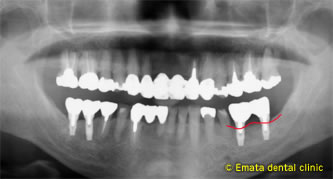

初期固定できる位置に埋入しました。

水平的 垂直的に骨造成するためチタンメシュをつかいました。

After

治療後 インプラントには骨が再生されています。